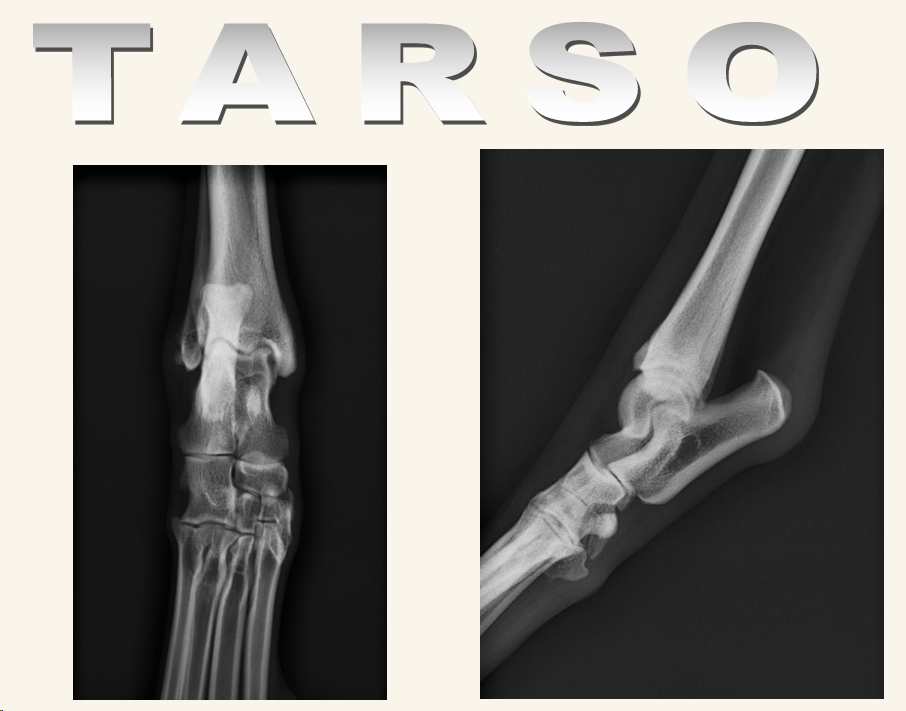

Tarso

Proyecciones ML y CdCr ó CrCd

Posibles problemas:

- Fracturas: Del maleolo, huesos tarsales, o tuberosidad del calcaneo. Se puede romper el calcaneo por estres al ligamento sobre todo, por su rotura por ejemplo. Si es antigua se ve calcificacion, si es antigua, solo inflamación

- Luxaciones

- Subluxacion Intertarsal: Escalon entre huesos centrales del tarso y articulacion con tibia, inflamacion del ligamento

- Problemas e shetland sheep dog. Puede haber cojera NO dolorosa con apoyo plantigrado

- Subluxacion tarso-metatarsiana: Esta SI produce dolor, inflamacion y cojera.

- Hiperextension, posbles fracturas proximales en metatarso. Radiografia en estres si se sospecha daño al ligamento

- Hiperextension o hiperflexion

- Recordad que cada hueso del tarso articulan, por tanto son susceptibles de tener enfermedades degenerativas musculares o EDA.

- Si lo atropellan pero frenan hay fracturas por abrasion, se come parte del hueso por arrastre. Se liman los huesos